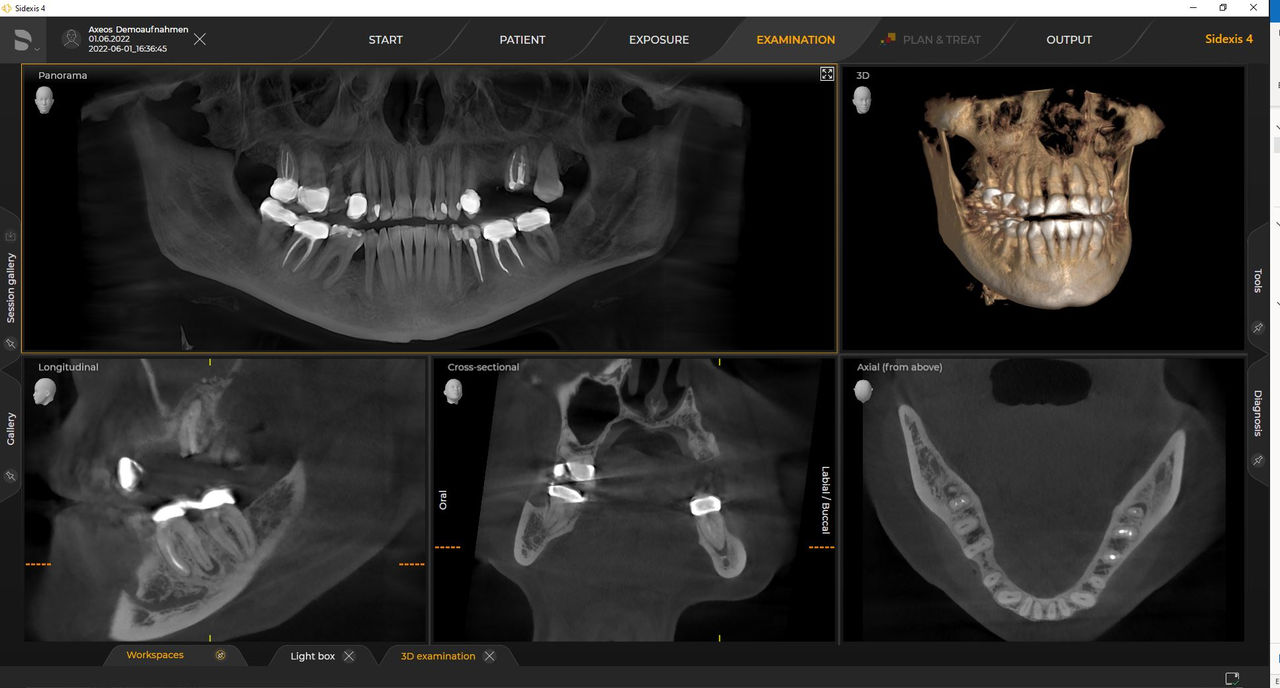

Axeos – the 2D/3D specialist system with a large volume and high image quality for practices with a broad treatment offering. Developed together with dentists and clinicians, Axeos provides the fullest range of functions out of all Dentsply Sirona extraoral X-ray devices. In addition to excellent image quality and tailor-made 3D volume sizes, the dental imaging device is fully optimized for enhanced patient comfort. Axeos not only provides quality in performance and comfort, but also with its award-winning design thanks to the integrated bite block accessory cabinet and ambient light.

Numerous volume sizes ensure flexibility in everyday practice. Examine a precise area or evaluate the complete dentition including the TMJs

Dentsply Sirona 3D units work exclusively with Sidexis 4. Nevertheless data migration from Sidexis XG to Sidexis 4 is very easy. Sidexis 4 allows for the full digital experience with the latest tools.